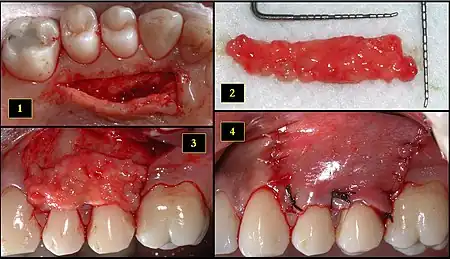

- Ipsilateral palatal mucosa serving as the donor site

- The retrieved connective tissue, approximately 25 × 6 mm in dimension

- Connective tissue placed at recipient site

- Recipient site flap coronally advanced and sutured to entirely cover the graft